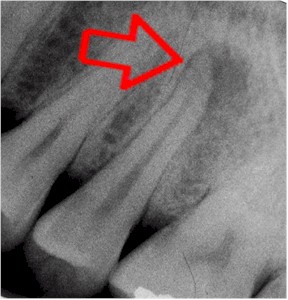

dental periapical xray

The dark shadow around the root of this tooth indicates a tooth abscess or infection